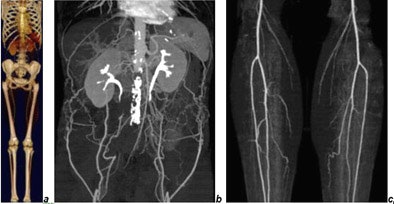

![]() |

| CTA of chest, abdomen, and legs (150-cm scan length) in a patient with Leriche's syndrome examined with 16 x 0.75-mm collimation within 50 seconds. Images courtesy of Dr. Mathias Prokop. |